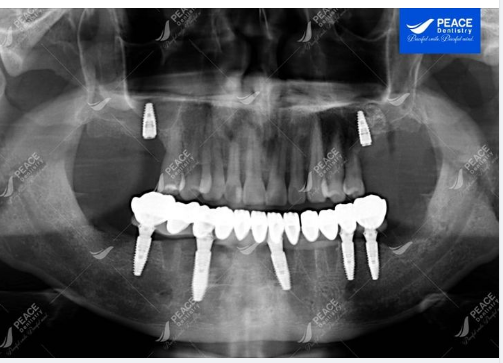

Cấy thêm 2 Implant hàm trên, R16, R26, phục hình sau 2 tháng.

✓ Hàm dưới: mất nhiều răng, chỉ còn lại một số răng tuy nhiên đều bị viêm nha chu nặng và nhiều năm dẫn đến tiêu xương, răng lung lay, lộ rõ chân răng (tiên lượng mất răng sớm)...dẫn đến suy giảm chức năng ăn nhai, đau nhức dai dẳng.

✓ Hàm trên: mất 4 răng hàm nhai, các răng còn lại có viêm nha chu nhẹ, có thể điều trị hiệu quả để giữ lại răng.

✓ Nhổ bỏ các răng hàm dưới (viêm nha chu nặng, tiêu xương, răng lung lay, tiên lượng mất răng sớm). Sau đó, cấy Implant tức thi với phương pháp All-on-5 Implant, phục hình tức thì hàm BioHPP

Sau 2 tuần điều trị, mặc dù chưa cố định răng cho 2 Implant được cấy ở hàm trên (R16, R26) nhưng với hàm dưới được khôi phục bằng giải pháp All-on-5 Implant + hàm BioHPP sức nhai đã đạt 80% - 90%, ăn nhai khỏe, cảm giác ăn nhai tốt, thẩm mỹ cao.